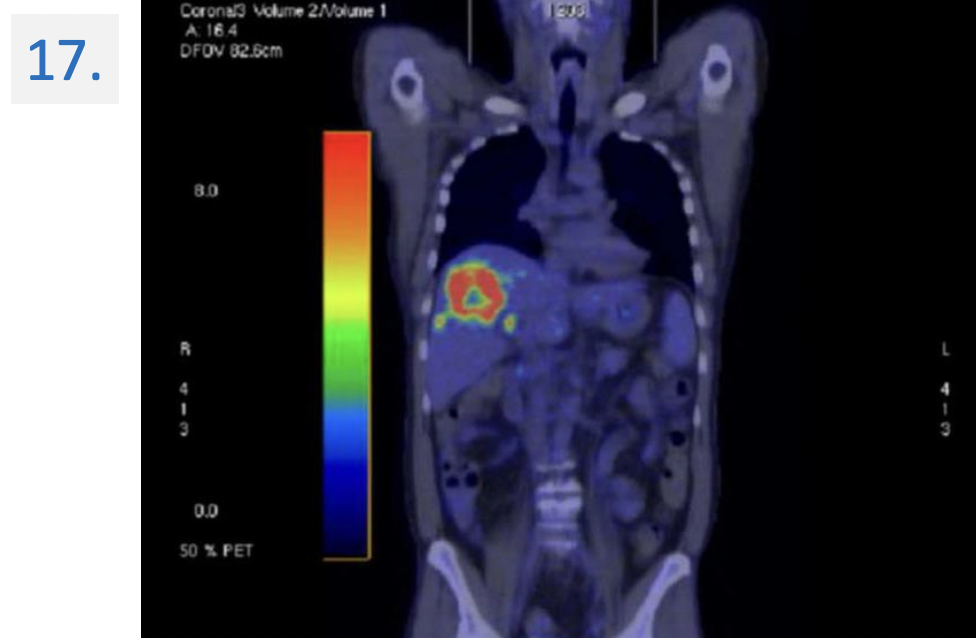

17

Modality:

FDG PET-CT (right panel: non-contrast CT) → 18(F)-fluoro-deoxy-glucose

Region:

upper abdomen, axial view

Diagnosis:

Malignant tumor → colorectal cc. metastasis → liver